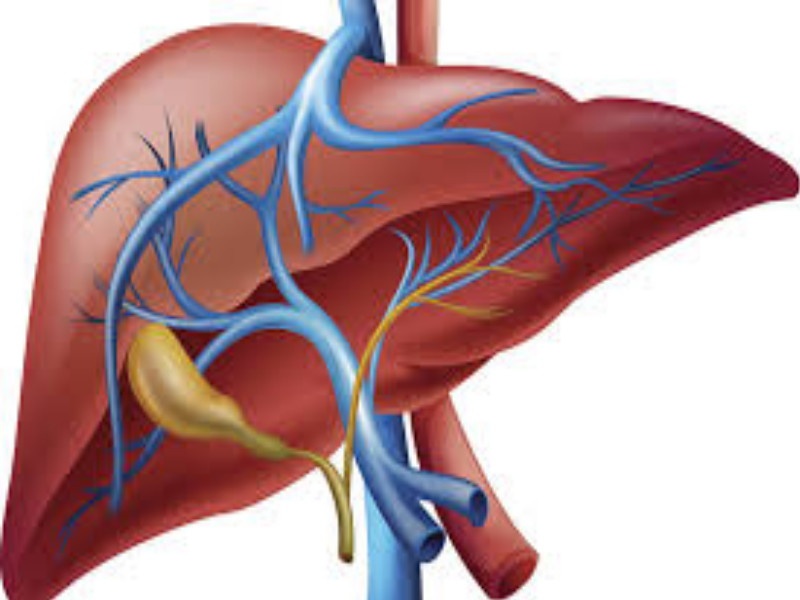

यकृताशी संबंधित आजाराने ग्रस्त किमान 5-10 रुग्ण दररोज दिसतात.

पुणे: निष्क्रिय जीवनशैली व आहारातील साखरेचे वाढते प्रमाण यामुळे शहरी भागात चरबीयुक्त यकृत रोग वेगाने पसरत आहे. येत्या काही वर्षांत या आजाराने प्रभावित लोकसंख्या वाढू शकते, अशी माहिती गॅस्ट्रो-इंटेस्टिनल सर्जन डॉ. हर्षल राजेकर यांनी दिली आहे. जागतिक यकृत दिनानिमित्त आयोजित कार्यक्रमात ते बोलत होते. यावेळी रुग्णालयाच्या महाव्यवस्थापक डॉ. विजू राजन उपस्थित होत्या.डॉ. राजेकर म्हणाले, यकृताशी संबंधित आजाराने ग्रस्त किमान 5-10 रुग्ण दररोज दिसतात. गेल्या 20 वर्षांत ही संख्या पाच पट वाढली आहे. ब-याच प्रकरणांमध्ये प्रारंभिक अवस्थेत त्या रोगात कोणतीही चिन्हे दिसू शकत नाहीत आणि म्हणूनच तो अज्ञात राहतो. सामान्यत: एखाद्या व्यक्तीच्या यकृतामध्ये 5 टक्के चरबी असते. यकृताच्या मूळ वजनाच्या 5 ते 10 टक्के वजनाचे यकृत असेल तर अशा चरबीयुक्त सामग्री असलेल्या व्यक्तींना सूजलेल्या यकृताच्या आजाराचा धोका अधिक असतो. या रोगामुळे यकृतामध्ये चरबी जास्त प्रमाणात जमा होते आणि अल्कोहोलमुळे आजारी पडण्याचा धोका वाढू शकतो. मधुमेह, लठ्ठपणा आणि चरबी यकृत रोगाचे प्राणघातक मिश्रण एखाद्या व्यक्तीच्या हृदयविकाराच्या झटक्याचे कारण बनवतो. पायांना सूज येणे, ओटीपोटात वेदना किंवा पोटदुखी, तसेच कमी भूक, वजन कमी होणे, शारीरिक कमजोरी आणि थकवा ही रोगाची काही लक्षणे आहेत.या रोगाच्या प्रतिबंधक उपायांमध्ये 30-40 मिनिटे एरोबिक व्यायामाचा समावेश करावा. याव्यतिरिक्त आपण योगाचा पर्यायदेखील निवडू शकता. शरीराचे वजन नियंत्रित करणे आणि हिरव्या भाज्या आणि फळे यांसह स्वस्थ आहारात जीवनशैली व्यवस्थापनासाठी महत्वाचे आहे. विटामिन ईचा वापर करुन मधुमेहावर अधिक चांगले नियंत्रण करता येते. जे फॅटी लिव्हरच्या आजाराची शक्यता 90 टक्के कमी करते. यकृत अल्ट्रासोनोग्राफी, कम्प्युटेड टोमोग्राफी स्कैन, मैग्नेटिक रेजोनेंस इमेजिंग व कंट्रोल्ड अटेनुएशन पैरामीटर यासारख्या निदान चाचण्यांद्वारे चरबी यकृत आजार ओळखता येतो, असेही डॉ. हर्षल राजेकर यांनी सांगितले.